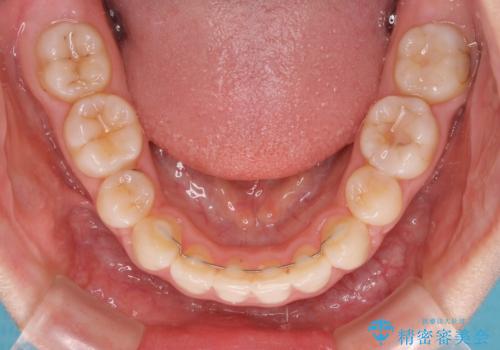

- 矯正装置

- クリアブラケット

- 治療期間

- 2年4ヶ月

- 矯正治療後の保定が不十分だと後戻り(元の位置に戻ろうとする動き)をします